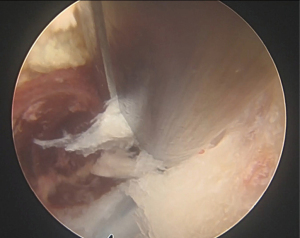

An approximately 1.0-cm vertical incision was made at 1.0 cm to the right of the midline, followed by the placement of an outer cylinder (external and internal diameter of the outer cylinder 9.9 and 8.9 mm, respectively). The endoscope (endoscope size: 8.4 mm, working channel size: 5.2 mm) was inserted in the outer cylinder. Sufficient bone of the lamina and bilateral facet joint at L3–4 was removed using a diamond bit drill and a Kerrison rongeur for the treatment of coexisting spinal canal stenosis. Approximately 10–15% of the medial corresponding facet joint, 7.0 mm of the caudal L3 lamina and 4.0–5.0 mm of the rostral L4 lamina at L4 (approximately 4.0–5.0 mm) were removed. An intraoperative chronic hematoma draining from the ligamentum flavum on the right side was visible during removal of the ligamentum flavum using a Kerrison rongeur for L4 nerve root decompression (Figure 2, Video 1). This chronic hematoma was confirmed to be discontinuous to the facet joint. The procedure was completed after confirming that the compression of the right L4 nerve root had been released and the drain tube was placed in the wound.

There have been some documented cases of full-endoscopic spinal surgery used to treat lumbar LFH (11,12). Intraoperative visualization of hematoma release from the ligamentum flavum, confirmed by FEL, can be helpful in successful decompression of intracanal pressure.